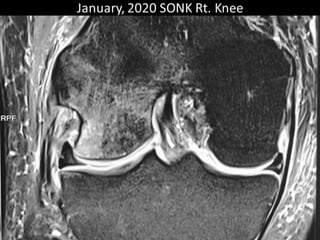

The document presents a detailed case study of a patient with transient osteoporosis of the hip (TOH) and spontaneous osteonecrosis of the knee (SONK) treated at Choithram Hospital & Research Centre in India. Over 20 years, the patient experienced multiple episodes of TOH and SONK with no history of trauma or co-morbidities, resulting in resolutions and recurrences of conditions. The information is intended for orthopedic surgery students and highlights personal experiences and case collections, with a disclaimer regarding content usage and potential controversies.